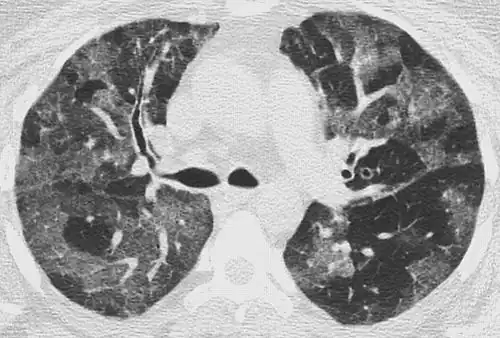

CT image in patient with COVID-19 showing bilateral ground-glass opacities at the periphery of both lungs.

Ground-glass opacity is among the most common imaging findings in patients with confirmed COVID-19.[16][17] One systematic review found that among patients with COVID-19 and abnormal lung findings on CT, greater than 80% had GGOs, with greater than 50% having mixed GGOs and consolidation.[16] GGOs with mixed consolidation has most often been found in elderly populations.[18] Several studies have described a pattern among initial, intermediate, and hospital discharge imaging findings in the disease course of COVID-19. Most commonly, initial CT imaging reveals bilateral GGOs at the periphery of the lungs. During initial stages, this is most often found in the lower lobes, although involvement of the upper lobes and right middle lobe has also been reported early in the disease course.[16][18] This is in contrast to the two similar coronaviruses, SARS and MERS, which more commonly involve only one lung on initial imaging.[19][20] As the COVID-19 infection progresses, GGOs typically become more diffuse and often progress to consolidation.[11][18] This is sometimes accompanied by the development of a crazy paving pattern and interlobular septal thickening.[18] In many cases the most severe pulmonary CT abnormalities occurred within 2 weeks after symptoms began.[17] At this point, many individuals begin showing resolution of consolidation and GGOs as symptoms improve. However, some patients have worsening symptoms and imaging findings, with further increase in septal thickening, GGOs, and consolidation. These patients may develop lung "white-out" with progression to acute respiratory distress syndrome (ARDS) requiring treatment escalation.[17][21]

Preliminary reports have shown many patients have residual GGOs at time of discharge from the hospital. Due to the novelty of COVID-19, large studies investigating the long-term pulmonary CT changes have yet to be completed. However, long-term pulmonary changes have been seen in patients after recovery from SARS and MERS, suggesting the possibility of similar long-term complications in patients who have recovered from acute COVID-19 infection.[22]